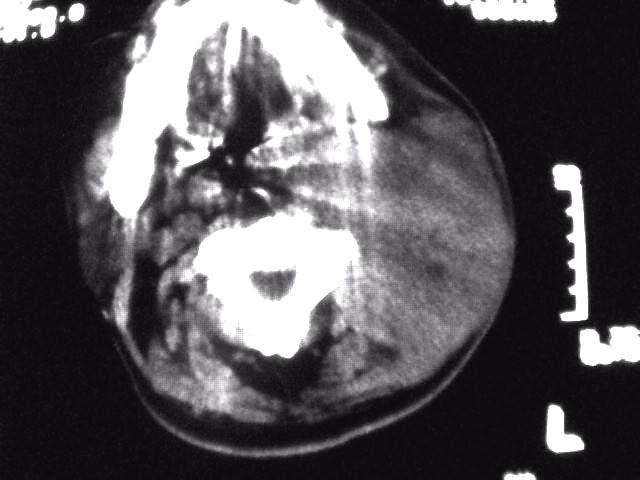

颈部层厚10mm间距10mm连续扫描及增强扫描共24层示:左侧下颈部胸锁乳突肌内侧区域内可见多发软组织结节,密度不均,内可见斑片状低密度区,大小不等,部分融合成块,左侧融合成一块者大约9.0x5.4,与周围肌肉、血管等结构界面不清,骨质未见明显浸润影。左侧锁骨下可见多个软组织结节,与周围界限尚清,左侧锁骨上窝内可见一大软组织肿物,大小约4.7x3.7cm,内密度欠均匀中心可见低密度区。

考虑:左侧颈部及双侧锁骨下多发淋巴结肿。非何杰金氏淋巴瘤可能性大,建议进一步检查。